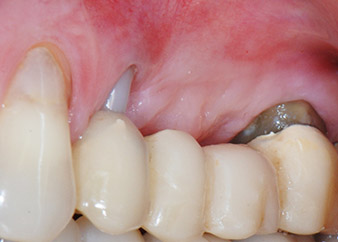

apikale Parodontalläsion an Zahn 24

Abb. 1: Bei einer 58-jährigen Patientin zeigt die Röntgenaufnahme vor der OP eine apikale Parodontalläsion an Zahn 24 und einen horizontalen Knochenabbau im zweiten Quadranten.

Eine 58-jährige Patientin, die auch eine gute Freundin und ärztliche Kollegin ist, beschwerte sich über Schmerzen und erhöhte Beweglichkeit ihres Brückenpfeilers 24. Es lag auch eine parodontale Entzündung vor, mit Taschentiefen von 7 mm mesiobukkal und mehr als 12 mm distal und einer Furkationsbeteiligung dritten Grades. Darüber hinaus zeigte die Röntgenaufnahme eine großflächige apikale Aufhellung am endodontisch (alio loco) vorbehandelten Zahn 24 (Abb. 1).

Ein Jahr zuvor waren die Zähne 25 und 26 vor dem Einsetzen der Brücke aufgrund traumatischer und endoparodontaler Ursachen extrahiert worden. Eine Paro-Endo-Läsion wurde bei unklarer ätiologischer Hauptkomponente für den Zahn 24 diagnostiziert. Die Patientin machte deutlich, dass sie ihre Pfeilerzähne 24 und 27 behalten und keinen endgültigen oder temporären herausnehmbaren Zahnersatz akzeptieren will. Darum wurde vereinbart, alles zu versuchen, beide Zähne, trotz der nach den radiologischen und klinischen Befunden als schlecht einzustufenden Prognose, zu erhalten.